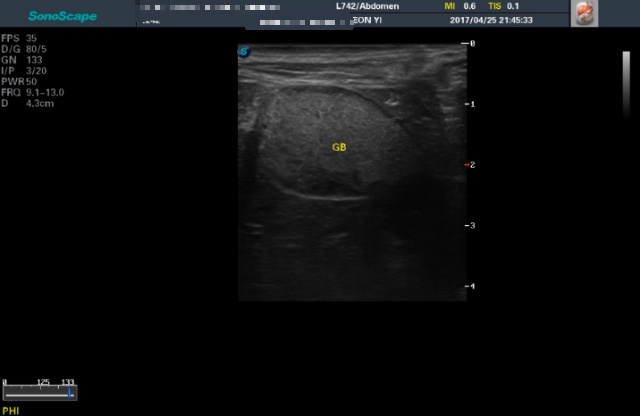

<4월25일 초진>

초음파상 하얗게 뒤덮여서 슬러지가 가득차있는 모습이었다가

5월 검진때 절반이 텅 빈걸 봤으니

유동적인 점액으로 확인된셈이네 안심하고 있던터인데..